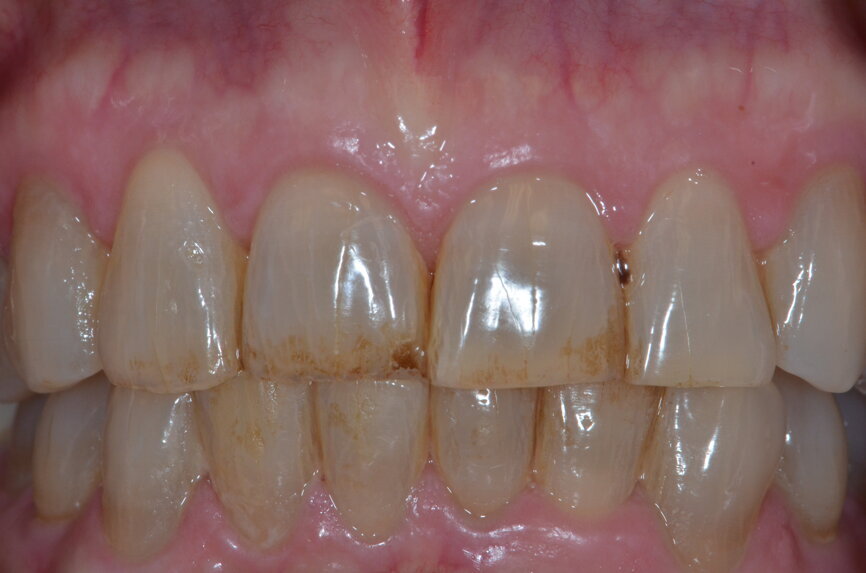

Fig. 19: Intra-oral photograph of conservative veneer preparations.

Minimally invasive preparation (0.5–0.8 mm facial reduction and 1.5 mm incisal/occlusal reduction) was done for the labial aesthetic veneers, allowing for enamel preservation (Figs. 18 & 19). A final impression was taken and the 3D virtual design was used as the preoperative digital model, since no modifications were done intra-orally after verification. Leucite glass-ceramic blocks (IPS Empress CAD, Ivoclar Vivadent) were milled for the final veneer restorations in-house using a milling machine (PlanMill 4.0, Planmeca; Figs. 20 & 21). Final characterisation was done after glazing.

At the delivery appointment, an aesthetic try-in was done prior to bonding the restorations. The patient approved the aesthetics, marginal fit was verified, and the teeth and restorations were etched and bonded (Variolink Esthetic, Ivoclar Vivadent). The patient was extremely satisfied with the treatment outcome (Figs. 22–25). An occlusal guard was provided as part of the treatment plan. At the one-year follow-up, the patient reported no complications.